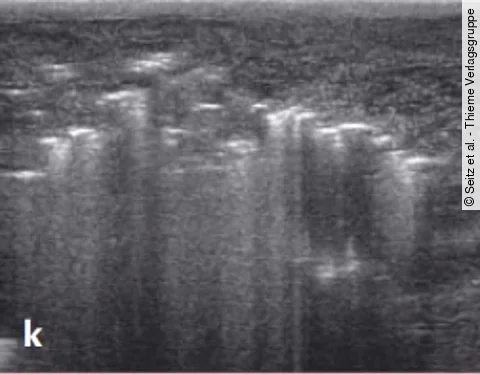

Multiple-Choice-QuizAuflösung: Schwierige Sonografie des Hodens

Es handelt sich um eine sehr schmerzhafte Diagnose.